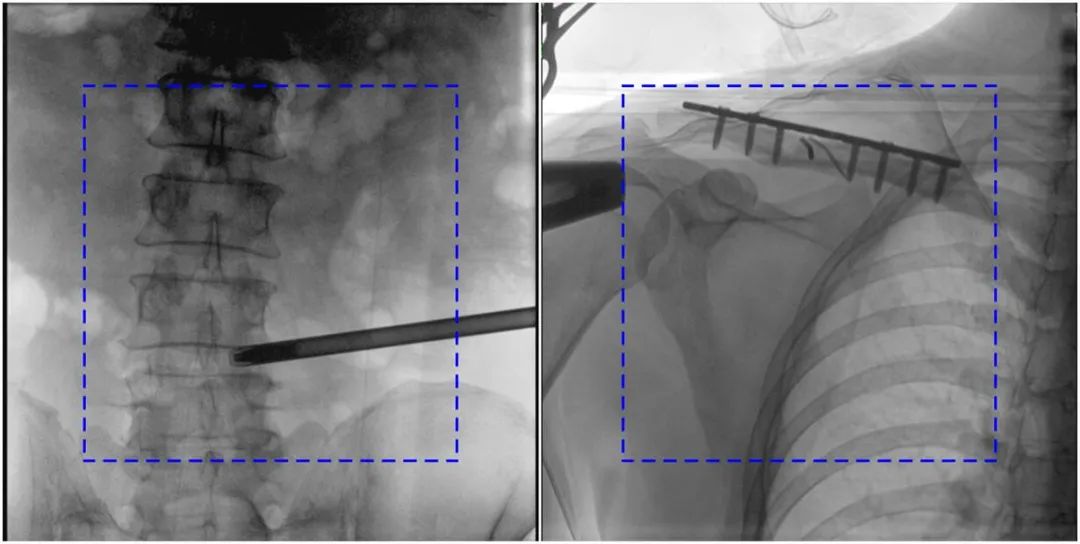

Compared with the traditional 21CM×21CM imaging size, Perlove's large flat-panel integrated C-arm has a larger imaging size of 30CM×30CM, capable of imaging 5.5 vertebrae at a time, presenting more comprehensive image information, even for young surgeons with little surgical experience, they can quickly determine the vertebral body segments and locate the surgical site through the image, avoiding multiple localization due to the insufficient field of view, Repeated exposure, improve efficiency and avoid excessive intake of radiation at the same time.

Comparison of Perlove's IntegratedLarge FPD C-Arm Images with Traditional Images

Note: The blue dotted line is the imaging area of the traditional 21CM×21CM flat panel.